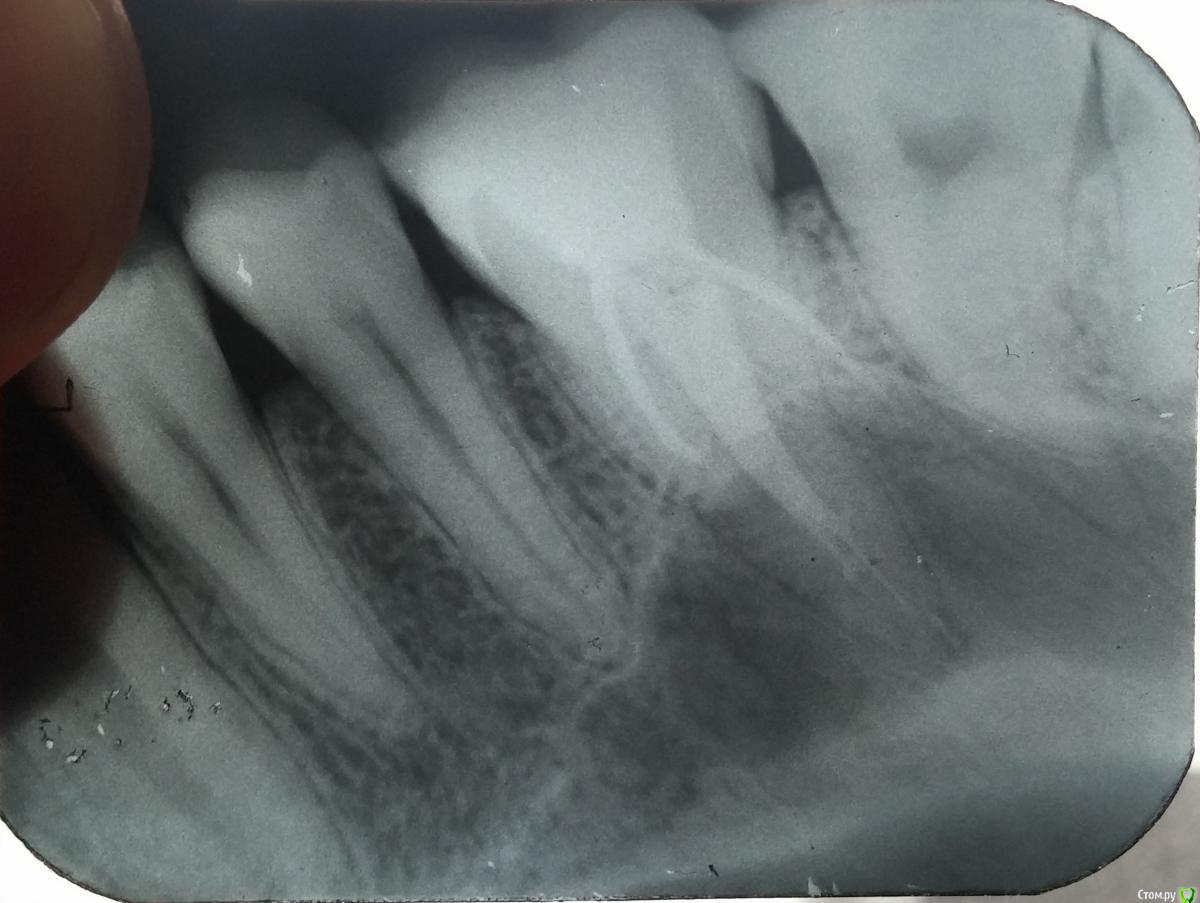

Metis2 Опубликовано 24 марта, 2015 Поделиться Опубликовано 24 марта, 2015 Здравствуйте уважаемые специалисты! Хочу обратится к вам с такой проблемой: год назад пошел на прием к стоматологу на профилактику, до этого не был у него 10 лет. В 6 сверху была большая дырка, поставили обычную пломбу, но зуб после лечения долго не проходил и я так проходил месяц пока боль стала нестерпимой. Как оказалось, воспалился нерв из-за того что стенка отделяющея нерв от пломба была очень тонкой. Когда мне чистили каналы та кашица, которую оттуда доставали была довольно зловонная, что насторожила стоматолога. После этого зуб начал проходить, но по неясной причине стала держаться температура 37,2-4 и держалась она у меня в течении двух недель. Спасался я только таблетками Нимид, после их приема температура спадала и на целый день мне хватало, мой врач на жалобы отвечала: мол это общее состояние организма, само пройдет, слава Богу прошло.Прошел ровно год после лечения и тут не с того не с сего начал болеть этот зуб, первые дни болел только при накусывании на него, а на третий день ныл и болел так, что я челюсть не мог закрыть. Я начал принимать Нимид - попустило. Но все равно боль была и при нажатии пальцем на десну сверху зуба, были болевые ощущения. Другой стоматолог предположил, что у меня переодонтит, сделали рентген, но он нечего не показал. На след.день зуб перестает болеть, даже если сжимаю челлюсть со всей силы. Но появилась эта странная температура, как и год назад и убирается она тем же способом, что и раньше, вот уже неделя температура, а зуб не болит, подскажите, что это может быть? Ссылка на комментарий

Гарриевич Опубликовано 24 марта, 2015 Поделиться Опубликовано 24 марта, 2015 1 вариант - пропустили 4 канала2 - недопломбировали (недомыли) небный каналаа может и то и другое Ссылка на комментарий

Goodman Опубликовано 24 марта, 2015 Поделиться Опубликовано 24 марта, 2015 8 слева сверху растет неровно, стоит ли удалять? он щеки не задевает, все норм, просто меня смущает его кривое расположение Ссылка на комментарий